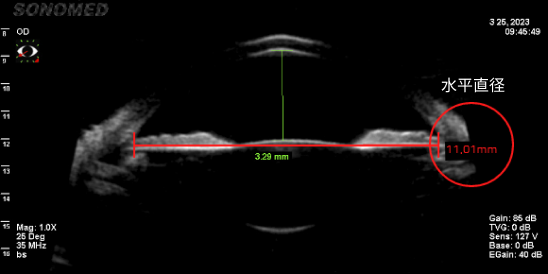

准确测量眼内空间

只有准确测量眼内空间是否足够,才能确定能否手术、晶体尺寸、可最小化晶体旋转概率的植入位置。

由于垂直直径平均比水平直径长,因此垂直型V-Toric ICL是在宽敞的空间内植入尺寸适中的晶体,晶体不接触周围组织,预防了晶体植入手术的副作用并提高了稳定性。

• 水平眼内空间测量(11.01mm)

• 垂直眼内空间测量(11.22mm)

垂直直径空间更广